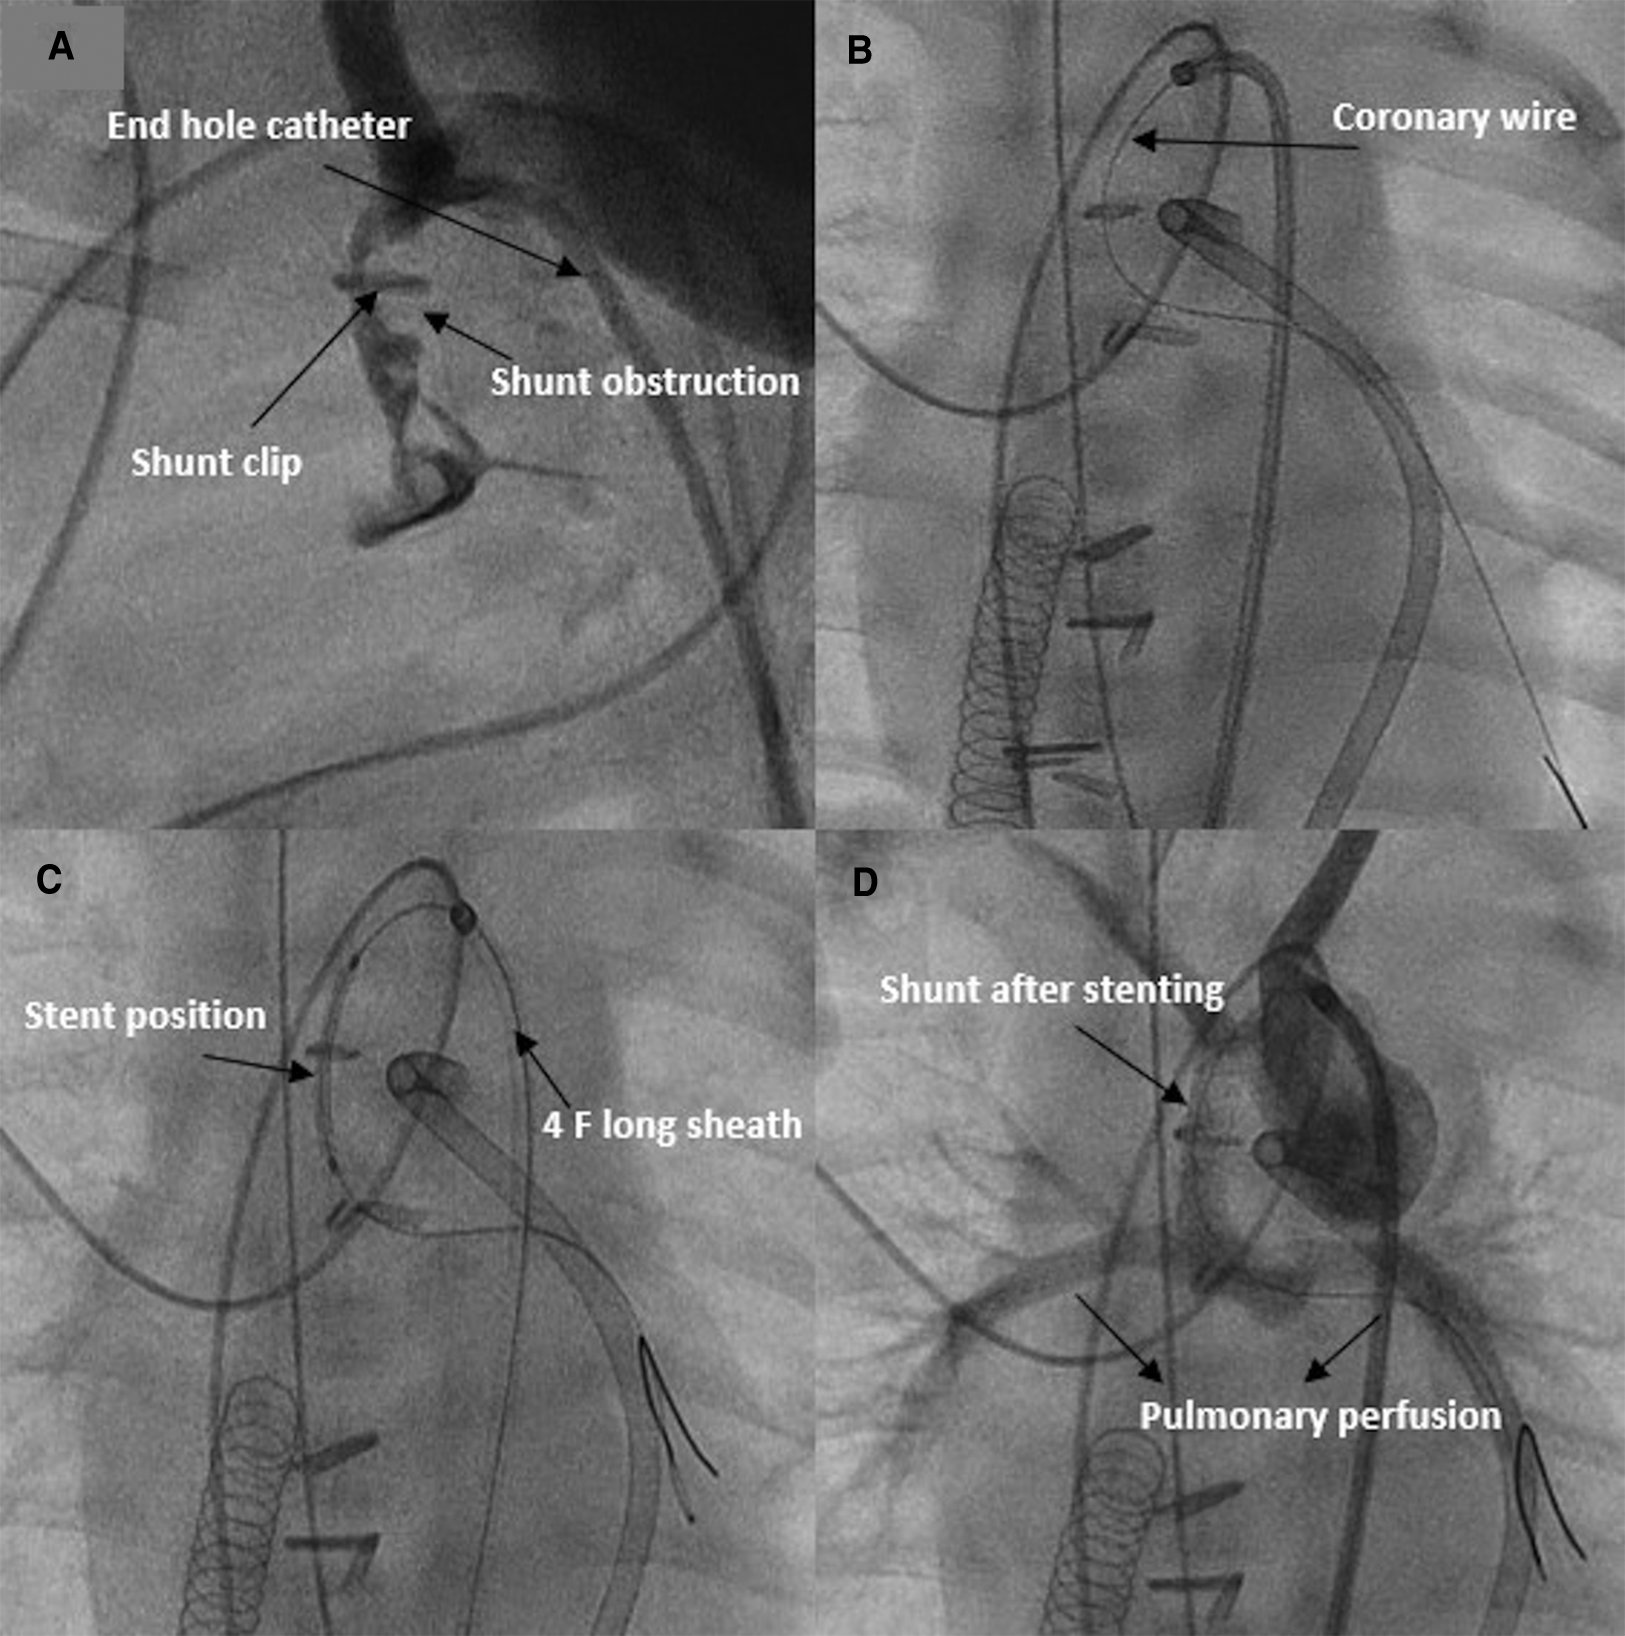

The second patient (HLHS) had an impaired thrombophilia diagnostic, which led postoperatively to multiple thrombotic events, including multiple cerebral thromboses and infarcts and thrombotic occlusion of the brachiocephalic vein. Stenting of the obstructed brachiocephalic vein with the need for redilation by acute thrombosis was required. The patient was resuscitated by acute obstruction of the shunt postoperatively, and the shunt stenting was performed by ECMO standby in the hemodynamically unstable child, who needed a high dose of catecholamine (Figure 5). Despite the continuous intravenous heparin, a new in-stent intervention was required due to thrombosis of the shunt stent and the pulmonary arteries, which occurred 30 days after stenting.

Figure 5

Revascularization and stenting of obstructed shunt postoperative. (A,B) Demonstrating the thrombosed shunt postoperatively in AP and lateral projection. (C) Recanalize the shunt with coronary wire and introduce the stent into the shunt. (D) Shunt and pulmonary perfusion after stenting.